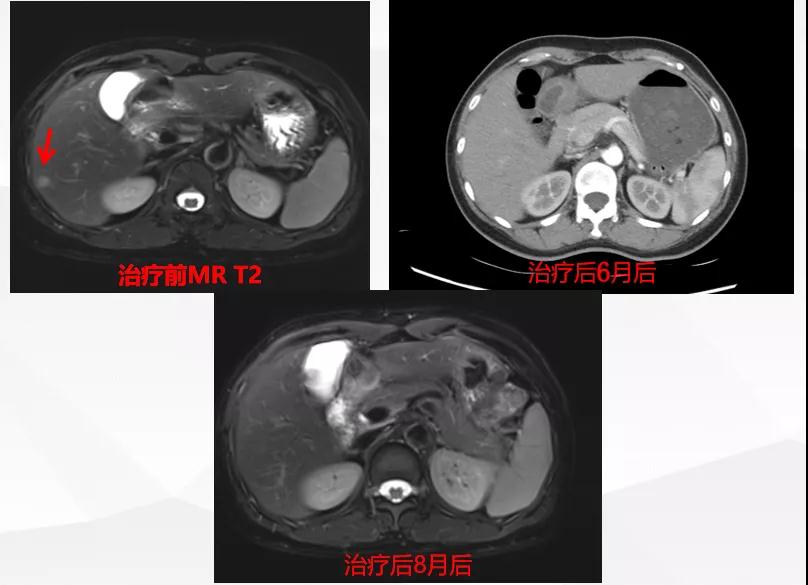

曲妥珠单抗辅助治疗结束6个月后,患者出现左侧胸部疼痛,ECT检查提示:左侧第4、5肋骨及T2胸椎转移;MR提示:T2椎体转移,肝S6段异常强化灶,考虑转移瘤可能性大;脑转移(图1)。

图1

给予T-DM1治疗。治疗6个月后复查MR显示脑、肝、骨转移瘤均较前明显缩小,达到部分缓解(PR)(图2)。目前PFS已达10+个月。

图2

患者为ⅢA期(cT3N1M0)、三阳性乳腺癌,经AC-TH新辅助治疗达到降期(ypT2N0M0)。患者内分泌+抗HER2辅助治疗结束6个月时出现转移进展(脑、肝、骨),给予THP一线治疗,因无法耐受毒副作用而改为T-DM1,治疗6个月达到肝、脑、骨转移PR,患者目前中位PFS已超过10个月,T-DM1治疗过程中仅出现轻度CIT,且可自行恢复。